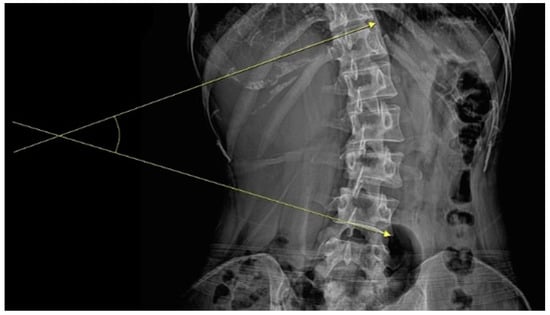

The inclusion criteria were as follows: (1) 19–65 years of age, (2) receipt of inpatient care at the study hospitals for the chief complaint of TA-induced LBP, (3) radiological (lumbar spine) findings of scoliosis and Cobb angle ≥10°, and (4) provision of voluntary verbal consent to participate in the study. Cobb angle was measured as the largest angle formed by the superior endplate of the superior end vertebra and the inferior end vertebra’s inferior endplate on anteroposterior lumbar radiographs (Figure 1) [].

Figure 1.

Measurement of Cobb angle.